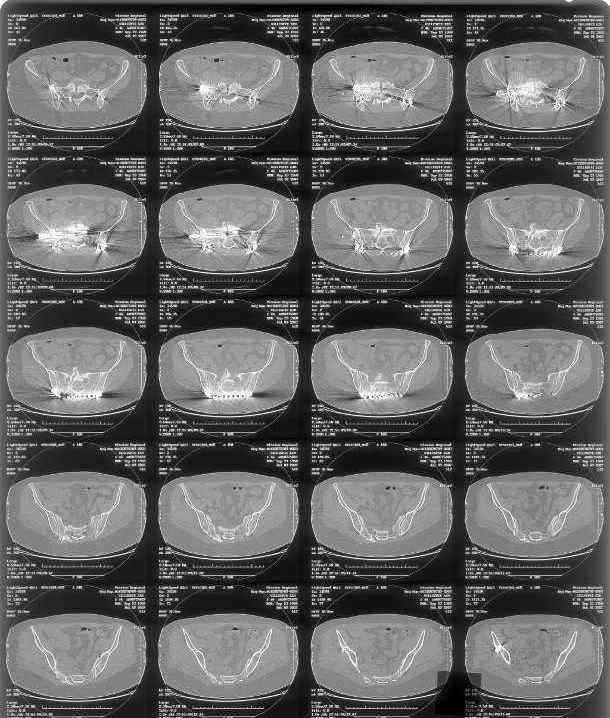

Here is a magnified view. Sorry about the quality but the CT was scanned into our system.

Thank you...it might help to remove the disengaged and other iliosacral screws then insert longer lag screws into the upper sacral segment and if anatomically feasible into the second sacral segment as well.

You could do it percutaneously and even add an electrical stimulation device if that seems reasonable.

At this point, I'd ignore the right pubic root issue if asymptomatic.

If simple measures such as those above fail, then you could remove it all, take down the sacral fracture site, refix with alternate techniques, and bone graft.